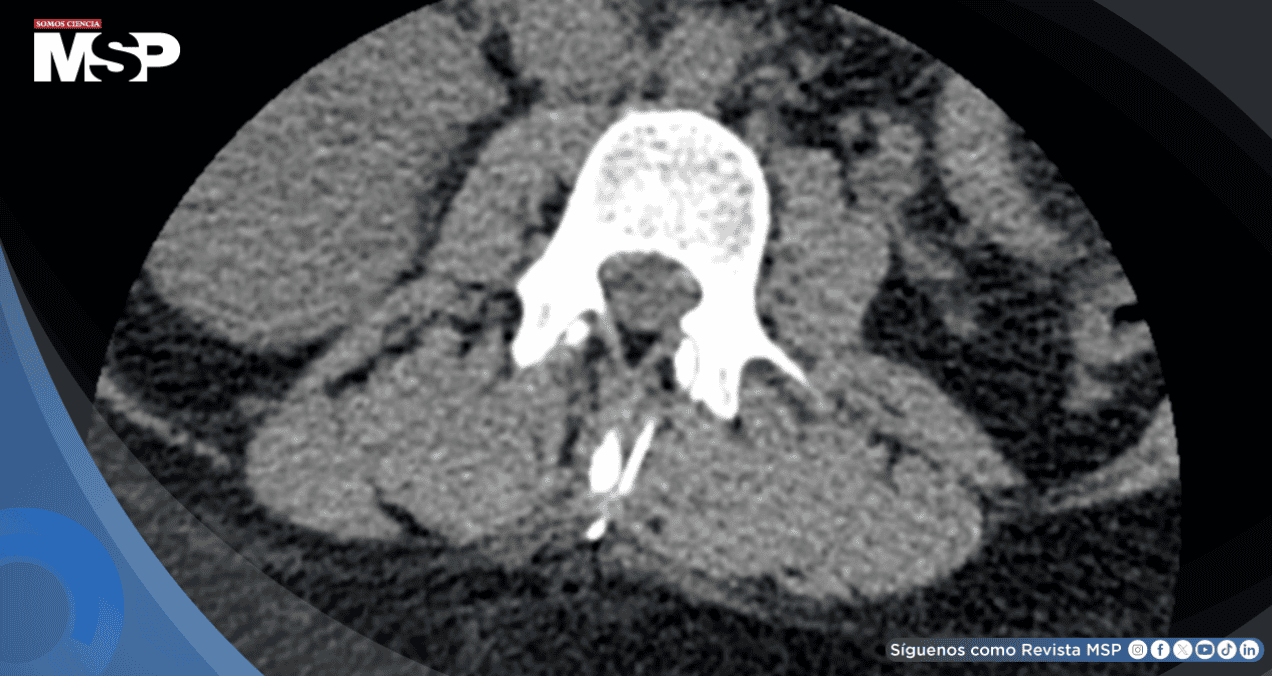

La tomografía computarizada confirmó la presencia del fragmento metálico lineal ubicado en la musculatura paravertebral a nivel L3, aproximadamente 1 cm lateral al proceso espinoso. No se identificó compromiso del canal espinal, hematoma epidural ni otras complicaciones asociadas. La localización superficial del fragmento fue determinante para la planificación terapéutica.